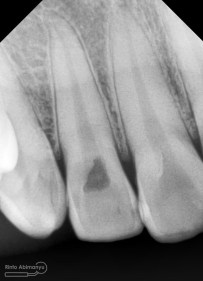

dan ini hasil ronsen nya..

Dari dua informasi klinis maupun radiografis saya sampaikan ke pasien bahwa kavitasnya sudah mengenai ruang saraf dari gigi tersebut, sehingga tidak mungkin langsung ditambal biasa. Singkat cerita saya jelasin deh tuh panjang lebar kenapa gak bisa langsung ditambal ( karena kalo saya tulis bisa kepanjangan… jelasin nya aja sekitar 20 menitan hehehehe )

Irigasi menggunakan larutan NaOCl 5,25% dan diaktivasi menggunakan ultrasonic dengan tip Irrisafe, setelah beberapa sequence selama hampir 40 menit kemudian dilakukan pengepasan guttap utama dan dironsen.

Dari ronsen semuanya terlihat sudah oke… dan siap dilakukan pengisian…